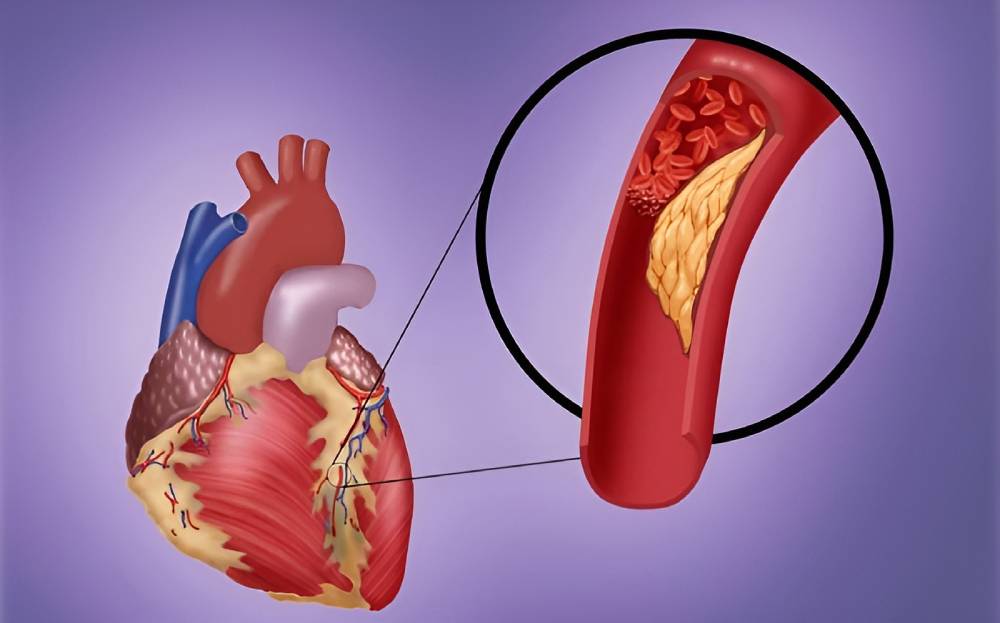

سکته قلبی یا انفارکتوس میوکارد زمانی رخ میدهد که جریان خون به قلب به شدت کاهش پیدا کند یا مسدود شود. این گرفتگی معمولاً پیامد جمع شدن چربی، کلسترول و مواد دیگر در شریانهای کرونری قلب است. به رسوبهای چرب و حاوی کلسترول پلاک گفته میشود. اصطلاح پزشکی برای فرایند تجمع پلاک تصلب شرایین یا آترواسکلروز است.

پلاک گاهی پاره میشود و لختهای را تشکیل میدهد که جریان خون را مسدود میکند. قطع شدن جریان خون به بخشی از عضلۀ قلب آسیب میزند یا آن را تخریب میکند.

انسداد ناقص عروق کرونر یا سکته قلبی ناقص (NSTEMI)

NSTEMI به اندازۀ STEMI جدی نیست، چون خونرسانی به قلب نه به صورت کامل، بلکه به صورت جزئی مسدود میشود. در نتیجه بخش کوچکتری از قلب آسیب میبیند. بااینحال NSTEMI همچنان یک مورد اورژانسی جدی محسوب میشود. انسداد ناقص عروق کرونری بدون درمان پیشرفت میکند و به آسیب قلبی جدی یا STEMI تبدیل میشود.

انسداد کامل عروق کرونر یا سکته کامل قلبی (STEMI)

STEMI جدیترین نوع سکته قلبی است که در اثر اختلال بلندمدت در خونرسانی به قلب رخ میدهد. STEMI نتیجۀ انسداد کامل شریان کرونری است که به آسیب گستردۀ بخش بزرگی از قلب منجر میشود. انسداد کامل عروق کرونر همان تصوری است که اکثر مردم از حمله یا سکته قلبی دارند.

اکثریت غالب سکتههای قلبی پیامد انسداد عروق خونی مسئول خونرسانی به قلب است. انسداد رگها غالباً نتیجۀ جمع شدن پلاک، یعنی مادۀ چسبناکی است که داخل شریانها جمع میشود. این اتفاق مشابه وضعیتی است که در اثر ریختن روغن داخل سینک آشپزخانه رخ میدهد و باعث گرفتگی لوله میشود. به تجمع پلاک آترواسکلروز یا تصلبشرایین میگویند.

رسوب پلاک درون شریانهای قلب (کرونری) گاهی متلاشی یا پاره میشود. ممکن است لختۀ خون در محل پارگی رسوب گیر کند. اگر لختۀ خون شریان را مسدود کند، خون به عضلۀ قلب نمیرسد و بیمار سکته میکند.